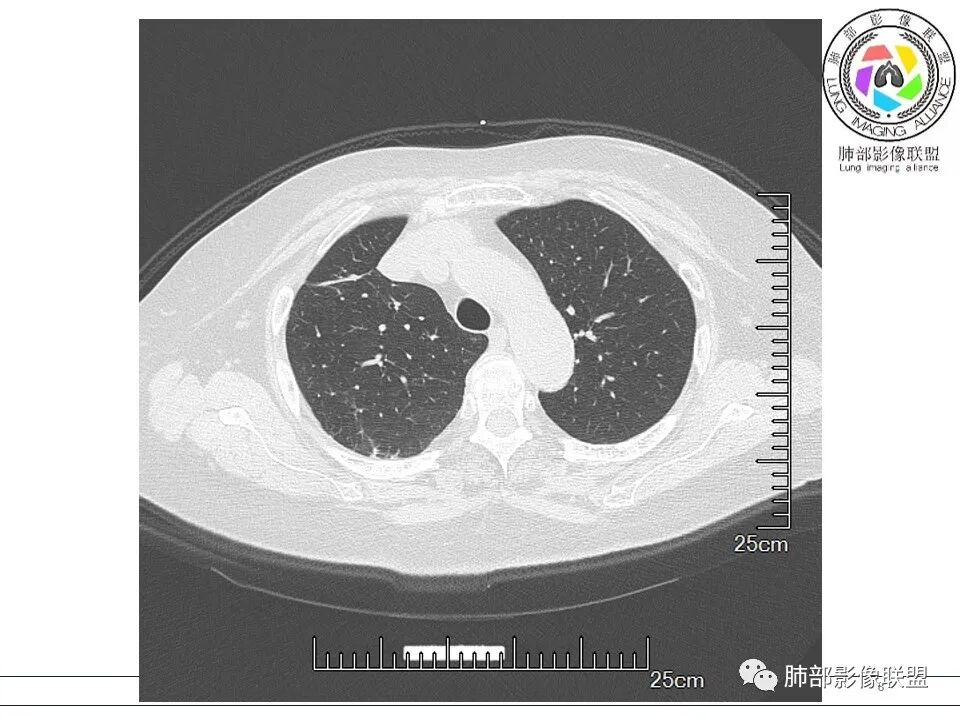

放射小白: 晨读病例:女性,70岁,风湿性多肌痛病史,右肺见不规则结节,边缘及周围见纤维索条影,考虑OP,药物性肺损伤。

小兜: 晨读,女,70岁,风湿性多肌痛病史一年,半月前体检发现肺部阴影,无症状,口服药物治疗。现片示:右肺胸膜下条形实变影,局部层面似见多结节融合,周边伴条索影。下方近叶间胸膜处斑片状实变影伴条索影,宽基底与胸膜相连。综合考虑为炎性病变,隐球菌或OP可能

宇宙: 右肺上叶胸膜下结节,多结节融合,长轴平行胸膜,边缘模糊,周围长索条,胸膜牵拉,近端支气管充气扩张,考虑隐球菌,鉴别OP

玫: 晨读:右肺上叶胸膜下软组织密度影,边缘模糊,周围见条索影及少许磨玻璃影,轻度胸膜牵拉,考虑炎性病变。

金豆 (刘权威): 右肺上叶胸膜下团块,支气管充气征,边缘纤维索条,磨玻璃,OP。

衡妈: 老年女性,右肺上叶沿胸膜下不规则实性病灶,长轴平行于胸膜,有结节融合感,边缘部分彭隆部分平直,周围可见数条纤维灶影,病灶内可见充气支气管征未达远端,首诊考虑慢性炎性肉芽肿,隐球菌?机化性肺炎?建议增强扫描及ct下穿刺活检。

放射线 (王秀仙): 右肺上叶胸膜下结节样影,边缘平直收缩,胸膜牵拉,支气管进入病灶并扩张,部分支气管进入后阻塞,长轴平行于胸膜,周围可见片状及条索状影,隐球?机化性肺炎?

晨读:女,70,未诉症状。风湿性多肌痛病史,口服强的松等药物治疗。胸部CT:右肺上叶多发不规则斑片影,沿支气管分布,部分病灶侧向融合、平行于胸膜,边缘平直内收为主、部分彭隆,周围模糊晕、可见数条纤维灶影,胸膜牵拉,病灶内可见充气支气管征、管腔不畅,考虑慢性炎症,PC?OP?鉴别腺Ca、SCLC等。

瑞欣 (刑瑞欣): 晨读,老年女性,右肺上叶不规则高密度影,可见胸膜牵拉,边缘光滑平直,与胸膜平行,周围条状影,可见支气管充气征,有风湿病史,考虑机化性炎症,鉴别隐球菌,腺癌

良孑: 右肺胸膜下多发结节,长轴与胸膜平行,部分病灶有多结节融合,可见近端支气管充气征,有晕征及晕中软毛刺,长期口服激素病史,抗炎效果欠佳。病灶形态单一,无播散性树芽,结节内无支气管穿行,单侧发病,收缩力差,可排除TB,OP及淋巴瘤,综和考虑支持隐球菌